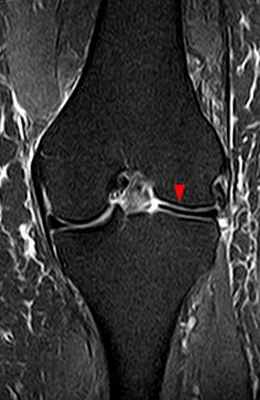

(Слева) МРТ Т2ВИ, режим подавления сигнала от жира, коронарный срез: у пациента 13 лет с болью в колене определяется неполный дискоидный латеральный мениск, который сужается к центру, но покрывает большую часть латеральной поверхности большеберцовой кости. Нормальный латеральный мениск должен покрывать около 50% поверхности большеберцовой кости.

(Справа) MPT PDВИ, коронарный срез: определяется частичный дискоидный медиальный мениск с горизонтальным разрывом. Дискоидные мениски имеют тенденцию к разрыву в большей степени, чем нормальные вследствие увеличения осевой нагрузки и трещины в неабсорбированных областях в центре фиброзного хряща. (Слева) МРТ PDВИ, последующие сагиттальные изображения: определяются признаки дискоидного латерального мениска. При использовании сагиттальных изображений толщиной 3-4 мм обычно не должно визуализироваться более трех полных срезов мениска до отделения переднего и заднего рога; у этого пациента таких срезов пять (самое медиальное изображение отсутствует).

(Справа) МРТ Т2ВИ, режим подавления сигнал от жира, коронарный срез: определяется дискоидный латеральный мениск, содержащий обширный патологический горизонтальный сигнал, указывающий на горизонтальный разрыв. (Слева) МРТ Т2ВИ, режим подавления сигнала от жира, коронарный срез: у пациента 10 лет определяется смещение разорванного дискоидного латерального мениска. Место прикрепления к капсуле разорвано, а более медиальная часть смещена кпереди от межмыщелковой вырезки.

(Справа) МРТ PDВИ, режим подавления сигнала от жира, сагиттальный срез: у этого же пациента определяется крупный латеральный фрагмент мениска в межмыщелковой вырезке с широким пучком повышенного сигнала внутри, характерным для горизонтального разрыва.

2. МРТ при дискоидном мениске коленного сустава:

• Коронарные изображения: утрата нормального сужения, клиновидная форма центрального мениска:

о Частичный дискоидный мениск суживается, но в медиально-латеральном направлении он шире, чем нормальный (>14 мм)

• Сагиттальные изображения: признак продолжающегося вещества мениска в передне-заднем направлении (зависит от толщины среза)